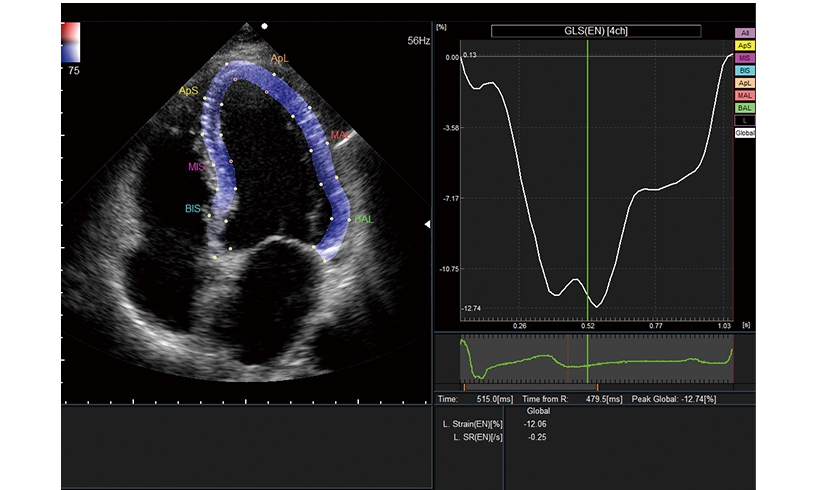

Automatically conducts various measurements via the 2D tracking method. The steps for ROI setting and analysis can be saved to shorten examination time significantly. Global Longitudinal Strain (GLS), which is attracting attention in heart failure examinations, can be measured easily.